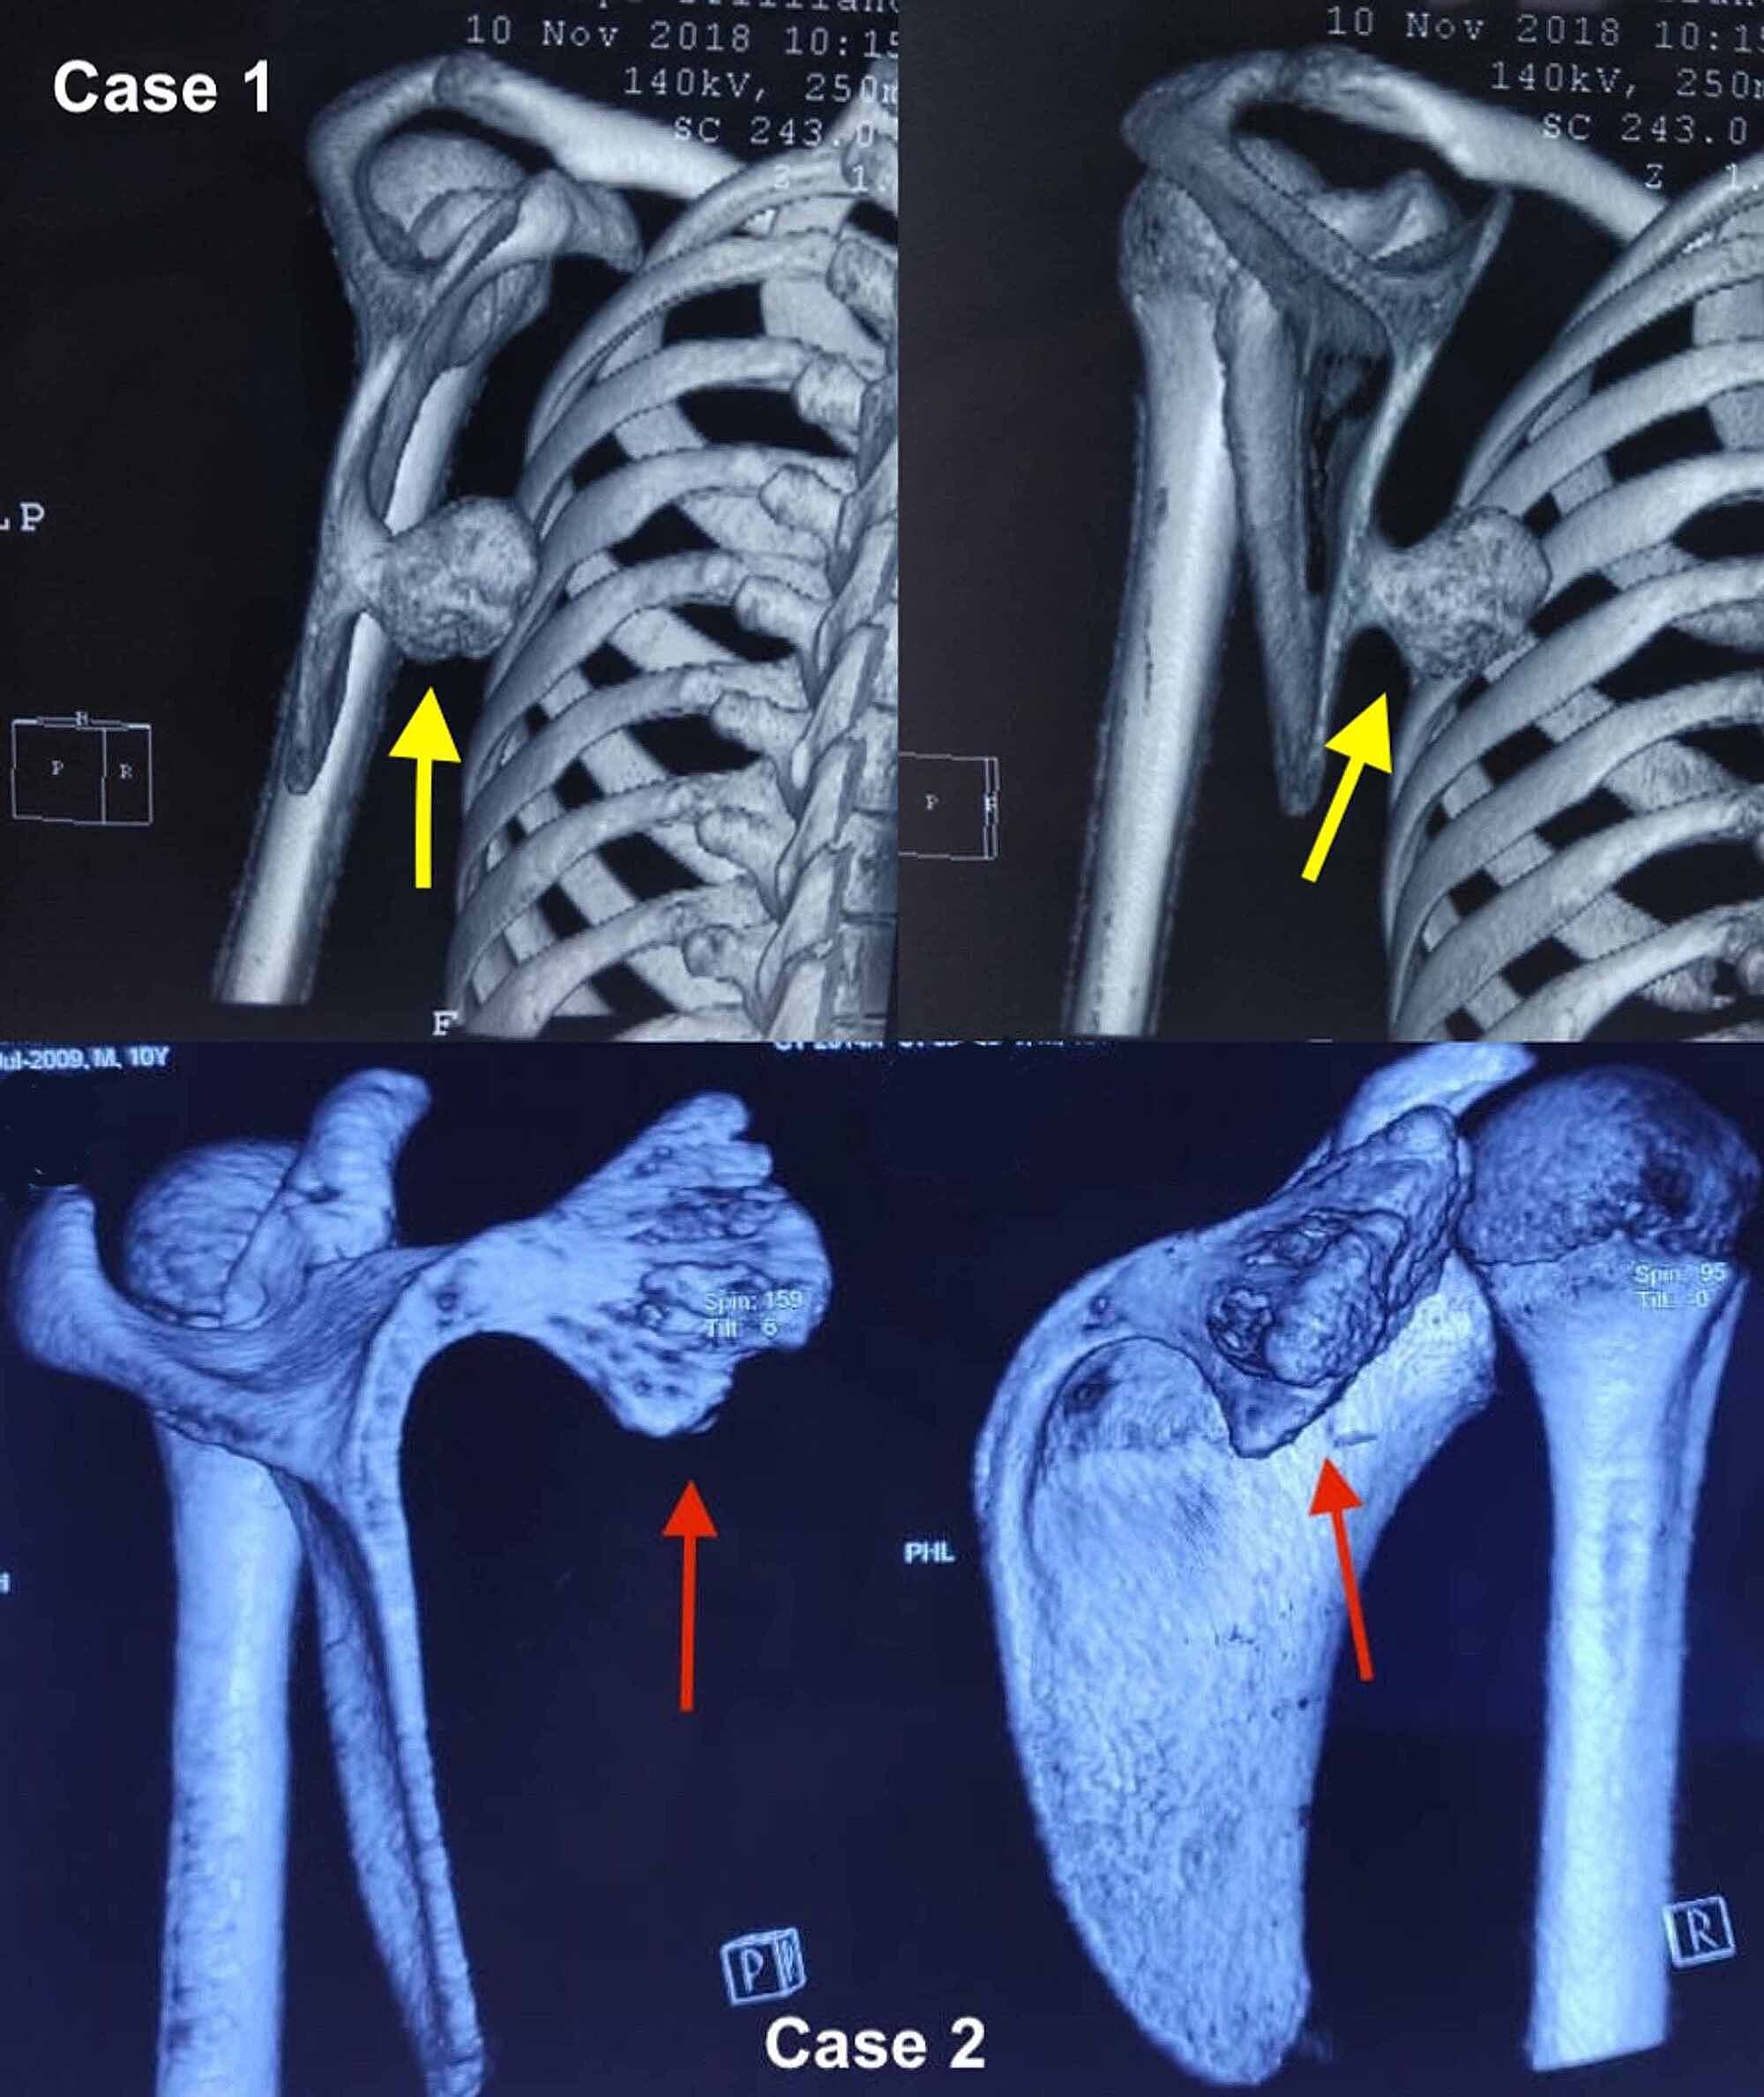

From www.cureus.com

Cureus Winging of Scapula An Presentation of a Common Tumor Scapula Bone Winging scapular winging happens when something stops your shoulder muscles and nerves from holding your shoulder blade. a winged scapula (scapula alata) is a skeletal medical condition in which the shoulder blade protrudes from a person's. the scapula, or shoulder blades, are flat bones that connect the upper arm to the collar bone. a primary winged scapula. Scapula Bone Winging.